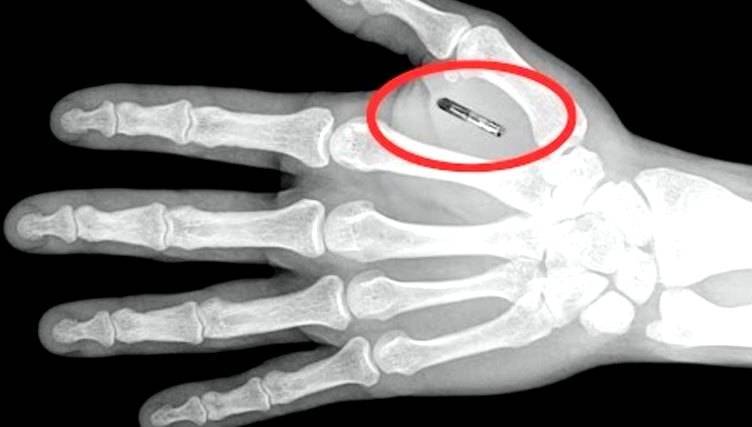

Датчик состоит из двух частей. Первой является 3-мм нить гидрогеля, вводимая под кожу с помощью шприца. Нить содержит специально сконструированную молекулу, которая меняет цвет, когда организм начинает бороться с инфекцией. Вторая часть - сенсор, крепящийся на кожу снаружи. Он сканирует нить и генерирует сигнал, при изменении ее цвета.